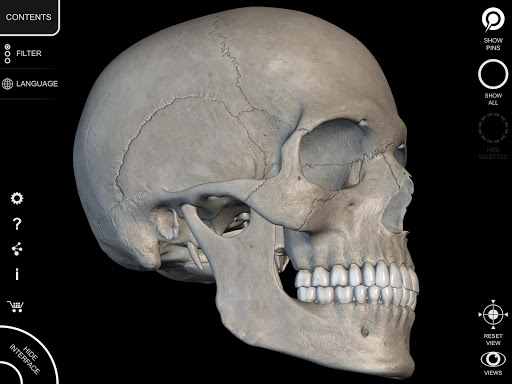

Mỗi xương của bộ xương người đã được tái tạo ở dạng 3D, bạn có thể xoay và phóng to từng mô hình và quan sát chi tiết từ mọi góc độ.

HÌNH GIẢI PHẪU 3D CÓ ĐỘ CHI TIẾT CAO

• Hệ thống xương

• Mô hình 3D chính xác

• Bề mặt của bộ xương có kết cấu độ phân giải cao lên đến 4K

• Xoay và Phóng to mọi mô hình trong không gian 3D